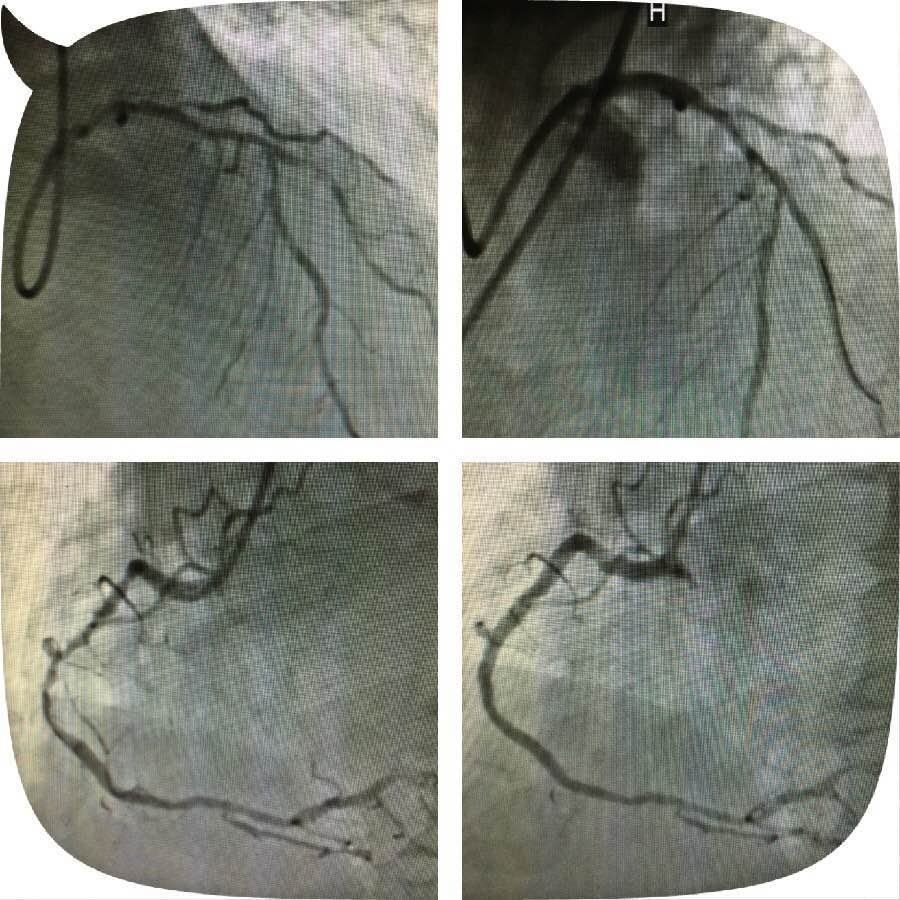

原来,这位老人突发心脏病被送到探花av 心五病区,入院后心电图示非ST段抬高心肌梗死,急诊行冠状动脉造影检查发现左主干钙化严重狭窄,合并右冠脉钙化严重狭窄病变,死亡风险极高。考虑患者病变复杂,贸然行左主干介入治疗风险极高,针对此患者特殊情况,心血管病医院组织专家进行缜密讨论,并与患者及家属充分沟通交流后,制定了血运重建的合理治疗方案。首先完成患者右冠脉钙化并严重狭窄病变的介入治疗,再次应用切割球囊行左主干严重钙化狭窄病变和对角支严重狭窄病变的介入治疗。

实施右冠严重狭窄长病变的介入治疗一周后,患者病情稍有缓解,经心血管病医院专家的缜密讨论,拟行切割球囊治疗患者的左主干钙化并严重狭窄病变,手术由心五病区郭瑄主任及陆艳副主任医师实施。术中如预期情况一样,经普通球囊反复扩张后,左主干的狭窄仍显得“纹丝不动”,患者出现胸痛症状,手术时间延长一分,患者手术风险增加十分,这时应用切割球囊就是关键的利器。手术成功!术中患者各项生命体征平稳,安返病房。